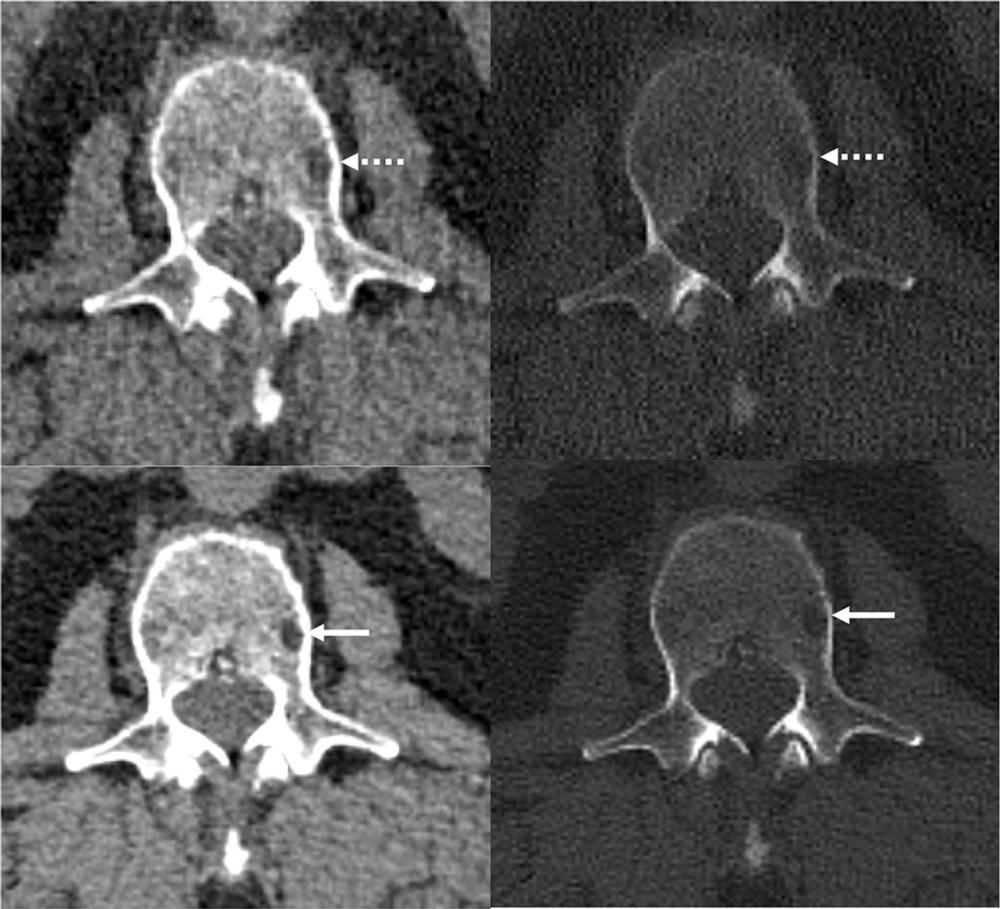

Figure 3. Reference protocol (top) and evaluated protocol (bottom) images in a 74-year-old man with multiple myeloma. The is the soft tissue reconstruction is shown, whereas the right column is the bone reconstruction. A lytic bone lesion in the L3 vertebral body is more conspicuous on the noncontrast-enhanced axial photon-counting detector CT reconstruction images (bottom; solid arrows) compared with the noncontrast-enhanced axial energy-integrating detector CT reconstruction images (top; dashed arrows).

Figure 4. Images in a 71-year-old man with relapsed multiple myeloma, after autologous stem cell transplant, who was administered single-agent daratumumab maintenance therapy. Foci of intramedullary hyperattenuation in the left proximal humerus with macroscopic internal fat suggested fatty metamorphosis of a multiple myeloma lesion after therapy. The degree of fat infiltration is better appreciated on the noncontrast-enhanced axial photon-counting detector (PCD) CT image (right), compared with the noncontrast-enhanced axial energy-integrating detector CT image (left). Beam hardening artifact (arrows), notably along the anterior cortex of the proximal humerus, is reduced on the PCD CT image.